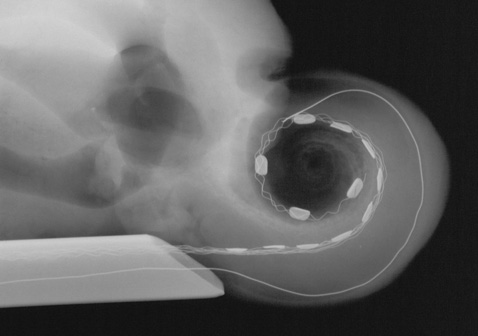

implant ślimakowy

Kliknij aby obejrzeć prezentację o umieszczaniu elektrod wewnątrz ślimaka [5,75MB]

Prezentacja przedstawiająca umieszczanie elektrod wewnątrz ślimaka ( ściągnij [5,75MB] )